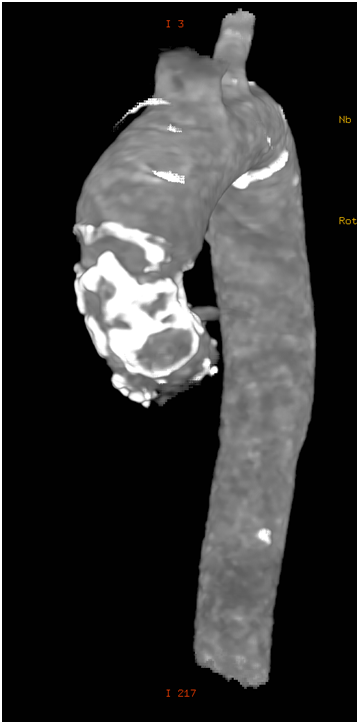

79 y old male patient, known to have diabetes mellitus, end stage renal failure and chronic obstructive pulmonary disease, this patient had aortic valve replacement (AVR) 15years prior, but because of infective endocarditis 7years ago, he underwent a redo AVR (Aortic valve Bioprosthesis) using a 25mm cry preserved aortic homograft implanted as a full root in another hospital. Patient was admitted with severe heart failure and pulmonary edema. His Echocardiogram showed severe AR (Figure 1). Patient was treated aggressively with anti-failure medications. The case discussed in heart team and both options AVR vs TAVI were raised in this high risk patient, with STS score 18. Both the heart team and Family preferred TAVI, According to sizing application this homograft valve will fit with Size 29mm Core Valve, The CT-scan measurements showed an aortic annulus size 21-25mm at different level, Perimeter range from 71-73, 3mm, Aortic valve area 2.9 cm2, and a heavily calcified a tube-like aorta (Figure 2). No clear sinus or junction was seen by CT. A trans-femoral approach for Valve in Valve was used. A 29 mm Medtronic Core valve was deployed and the landmark was the calcium in the root. Unfortunately, it migrated up-ward most probably due to the rigidity of the homograft tube and no real narrowing or calcified leaflet to anchored the valve (Figure 3). Therefore we used another 29 core valve and deployed it through the first one which was well seated in ascending aorta as support. This method of support was very successful for final deployment (Figure 4). It was similar to the melody valve deployment in treating pulmonary regurgitation. There was no aortic regurgitation by Echocardiogram (Figure 5). Patient was very stable and discharged home after 48hours.

Figure 2 Ct-scan image of ascending aorta with heavy calcification and full root replacement.